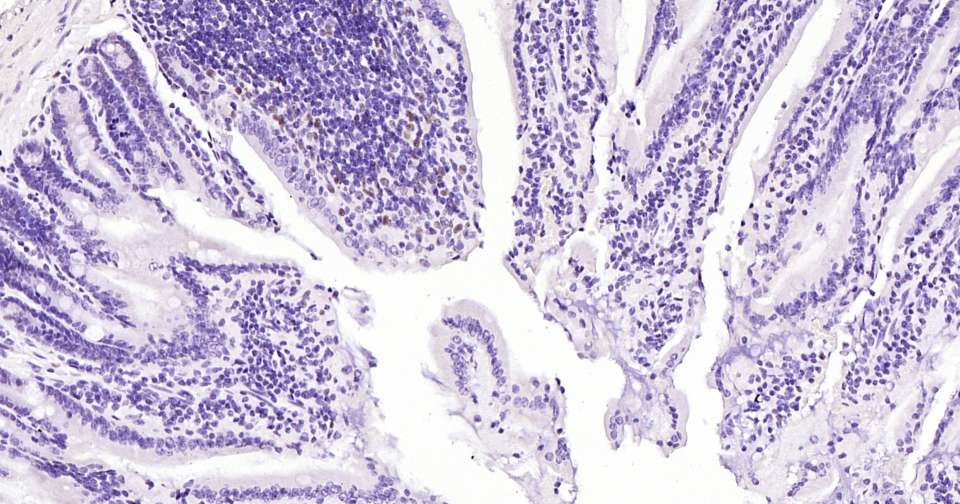

Immunohistochemical analysis of paraffin embedded mouse small intestine tissue slide using IHC0325 (Cyclin D1 Kit).

Immunohistochemical analysis of paraffin embedded human colon cancer tissue slide using IHC0325 (Cyclin D1 Kit).

Immunohistochemical analysis of paraffin embedded rat small intestine tissue slide using IHC0325 (Cyclin D1 Kit).